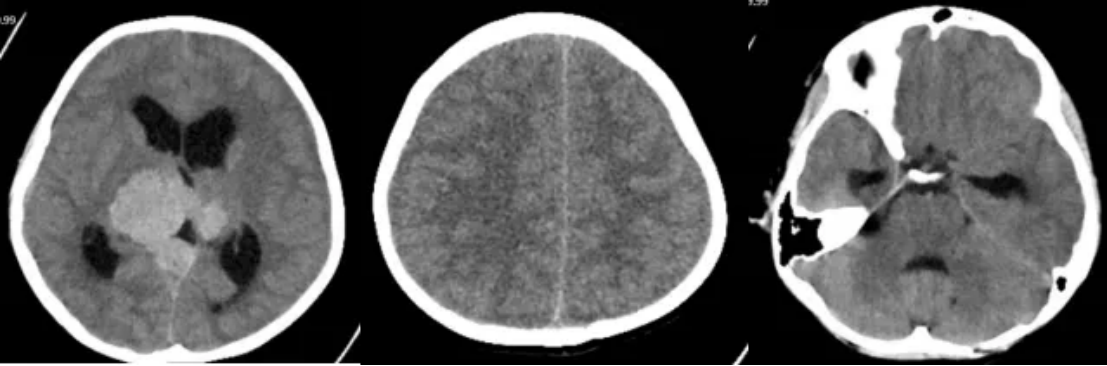

2023年10月7日患者无诱因出现恶心、呕吐、精神差,肢体乏力,无视物模糊、视物缺损等症状入院,并于10月12日和16日进行MR和CT检查(图3-4),结果提示:肿瘤复发并梗阻性脑积水。

图3 复发后MR检查

图4 复发后CT检查